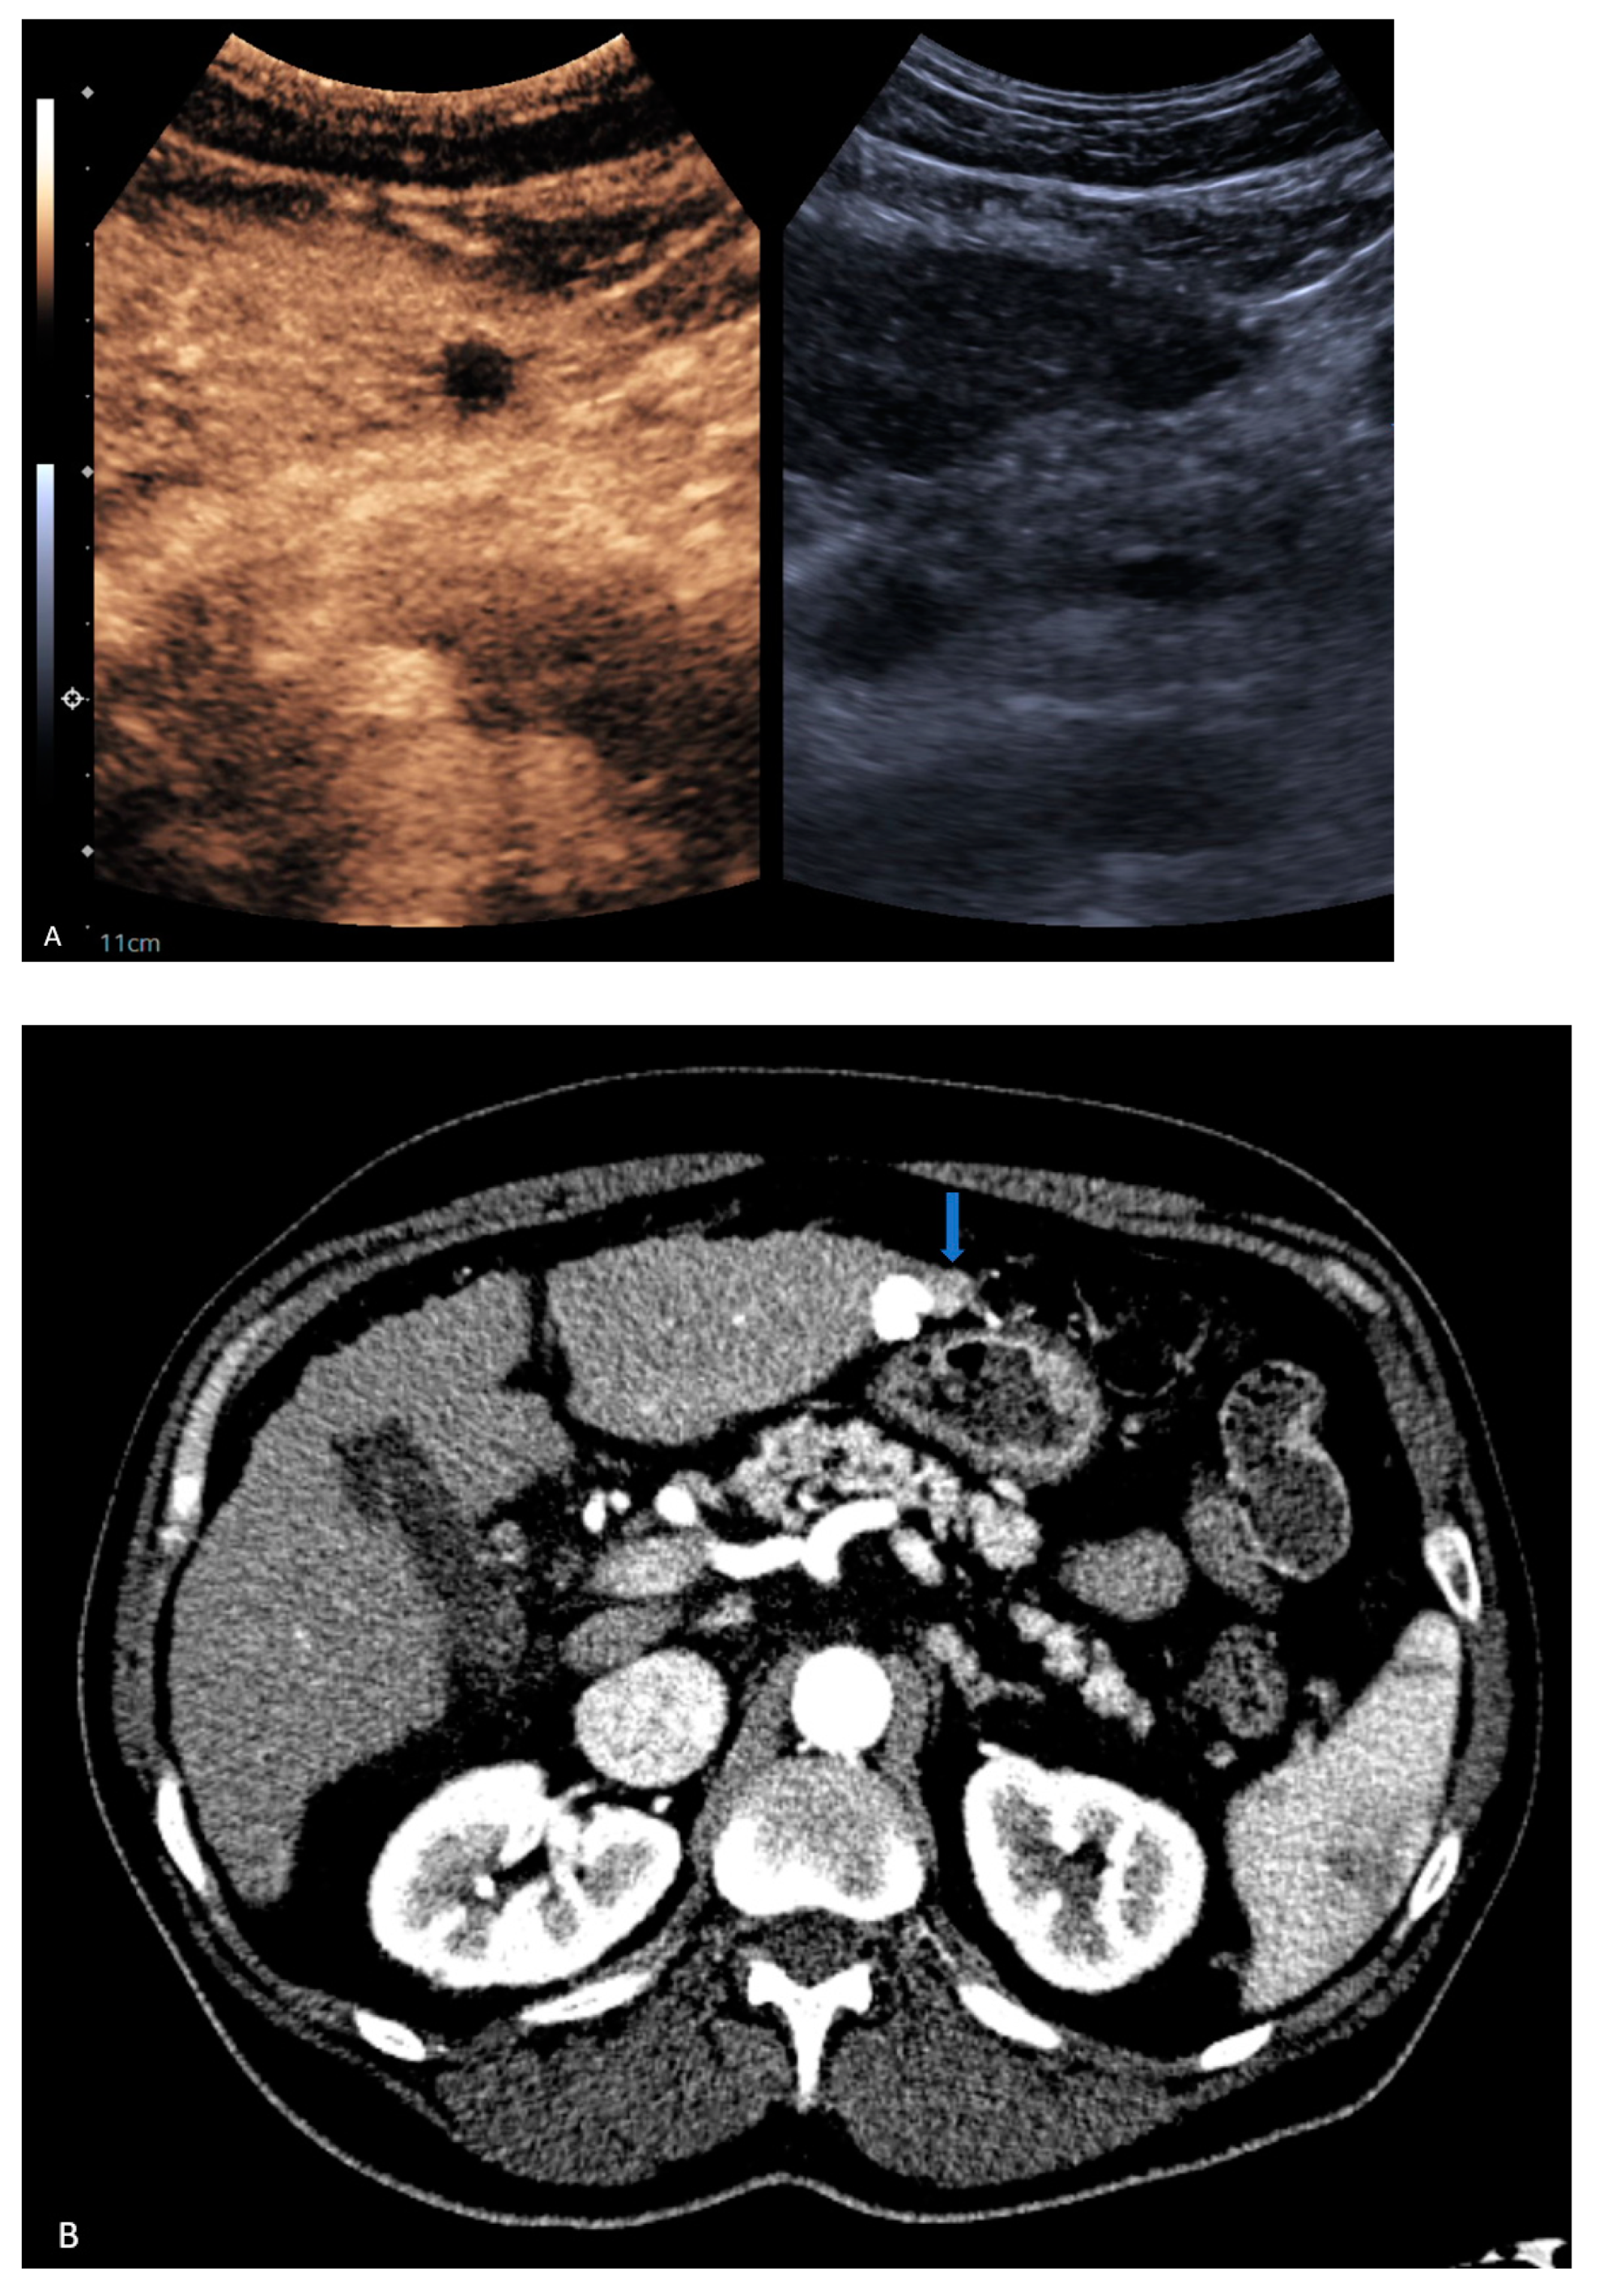

| 4 | CT | Target | LR-treated | CEUS called residual tumor (Figure 1), follow-up CT confirmed treated tumor |